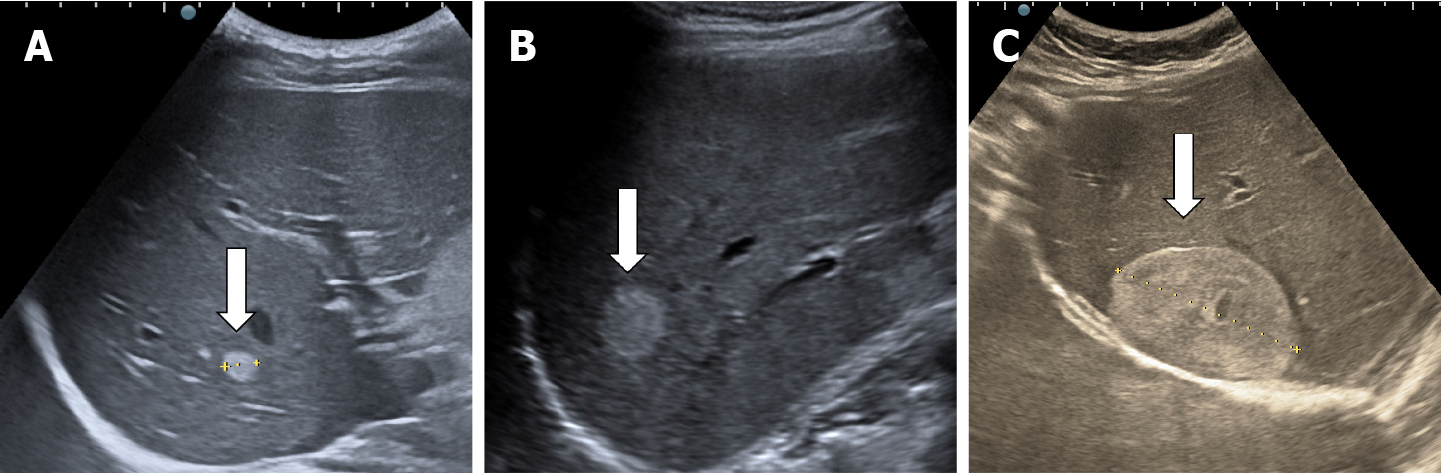

Grades of fatty liver on visual analysis. Ultrasound image shows (a) Normal liver echogenicity (b) Grade 1 fatty liver with increased liver echogenicity (c) Grade 2 fatty liver with the echogenic liver obscuring the echogenic walls of the portal venous branches (d) Grade 3 fatty liver in which the diaphragmatic outline is obscured

Fatty liver should be charted as echogenic liver. Difficult to penetrate. Consistent with Fatty liver.